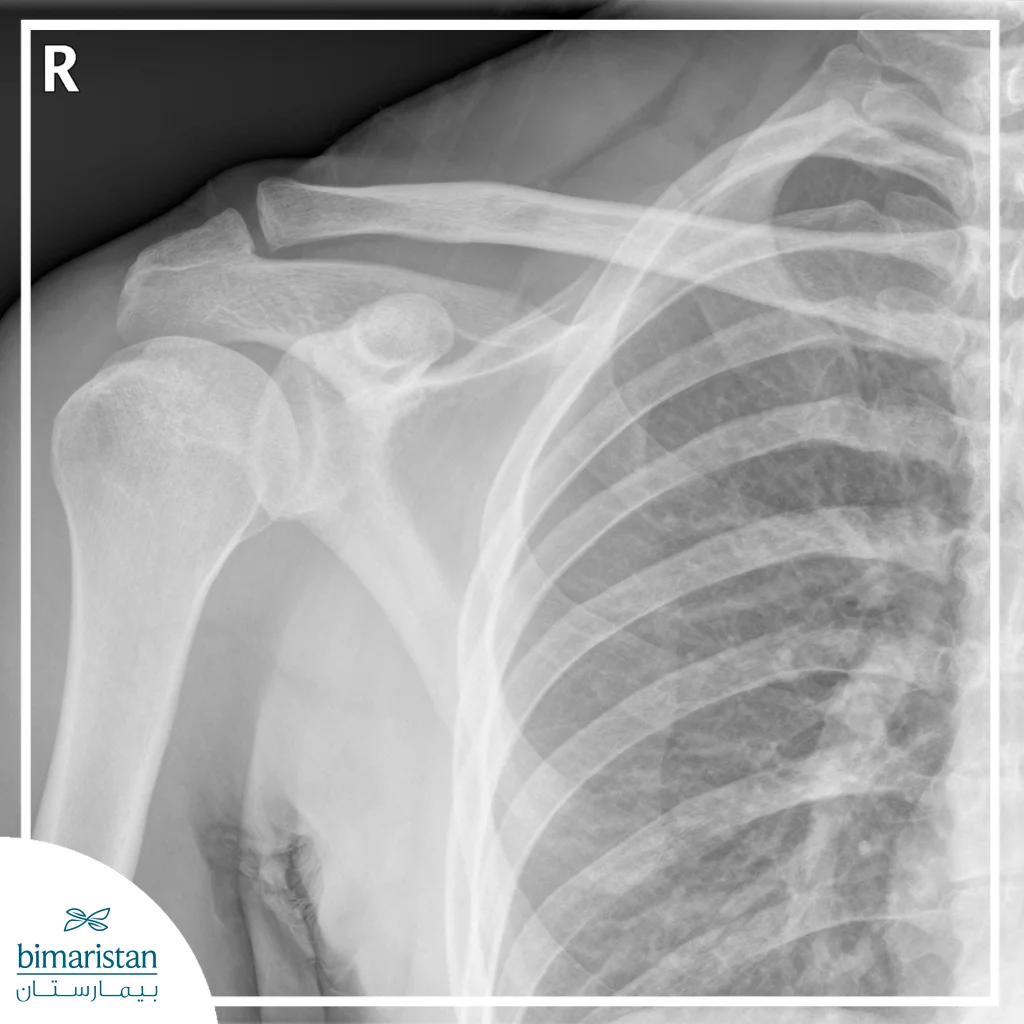

الأشعة السينية

تعتبر الأشعة السينية الطريقة الأكثر شيوعاً لتشخيص كسور الكتف، حيث تُظهر العظام بشكل واضح وتكشف عن مكان الكسر ونوعه (بسيط أو معقد)، تساعد الصور الشعاعية الأطباء على تحديد مدى انزياح العظام، وتقدير الحاجة لتثبيت الكسر جراحياً أو علاج تحفظي.